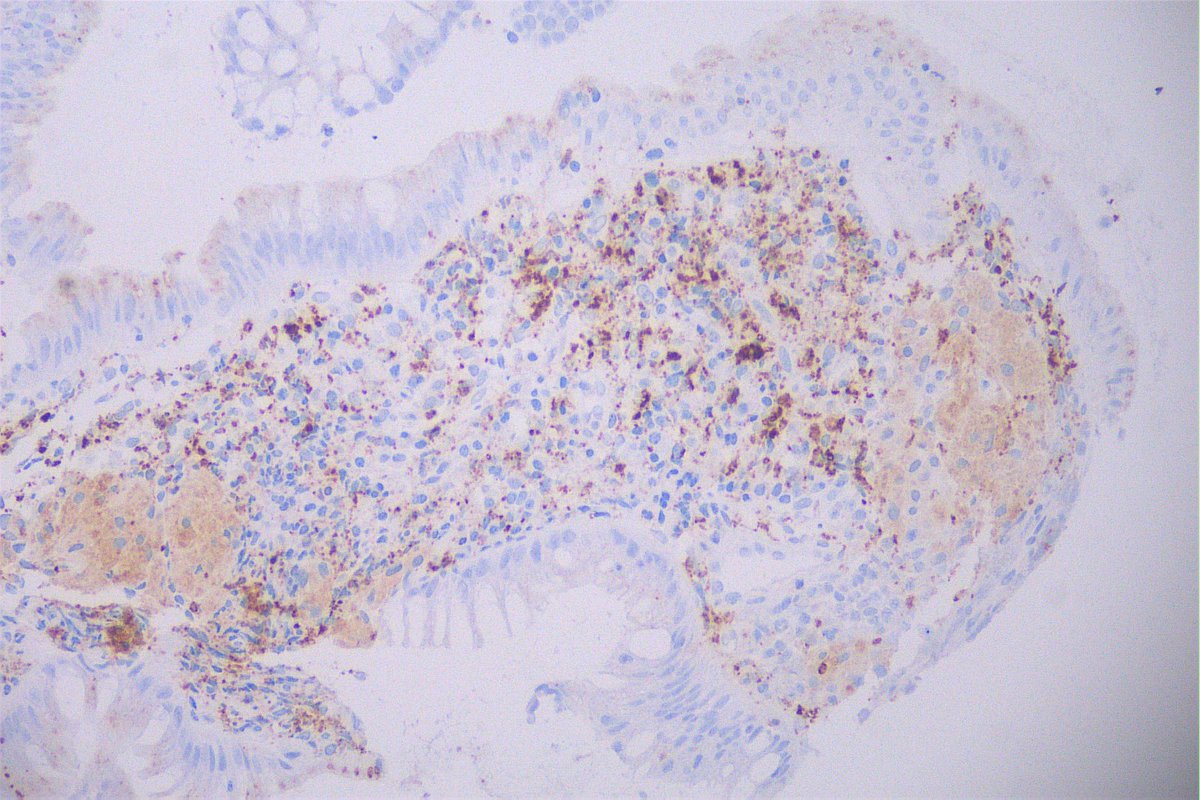

@GeronimoJrLapac

Ger么nimo Jr.

2 months

Cd68